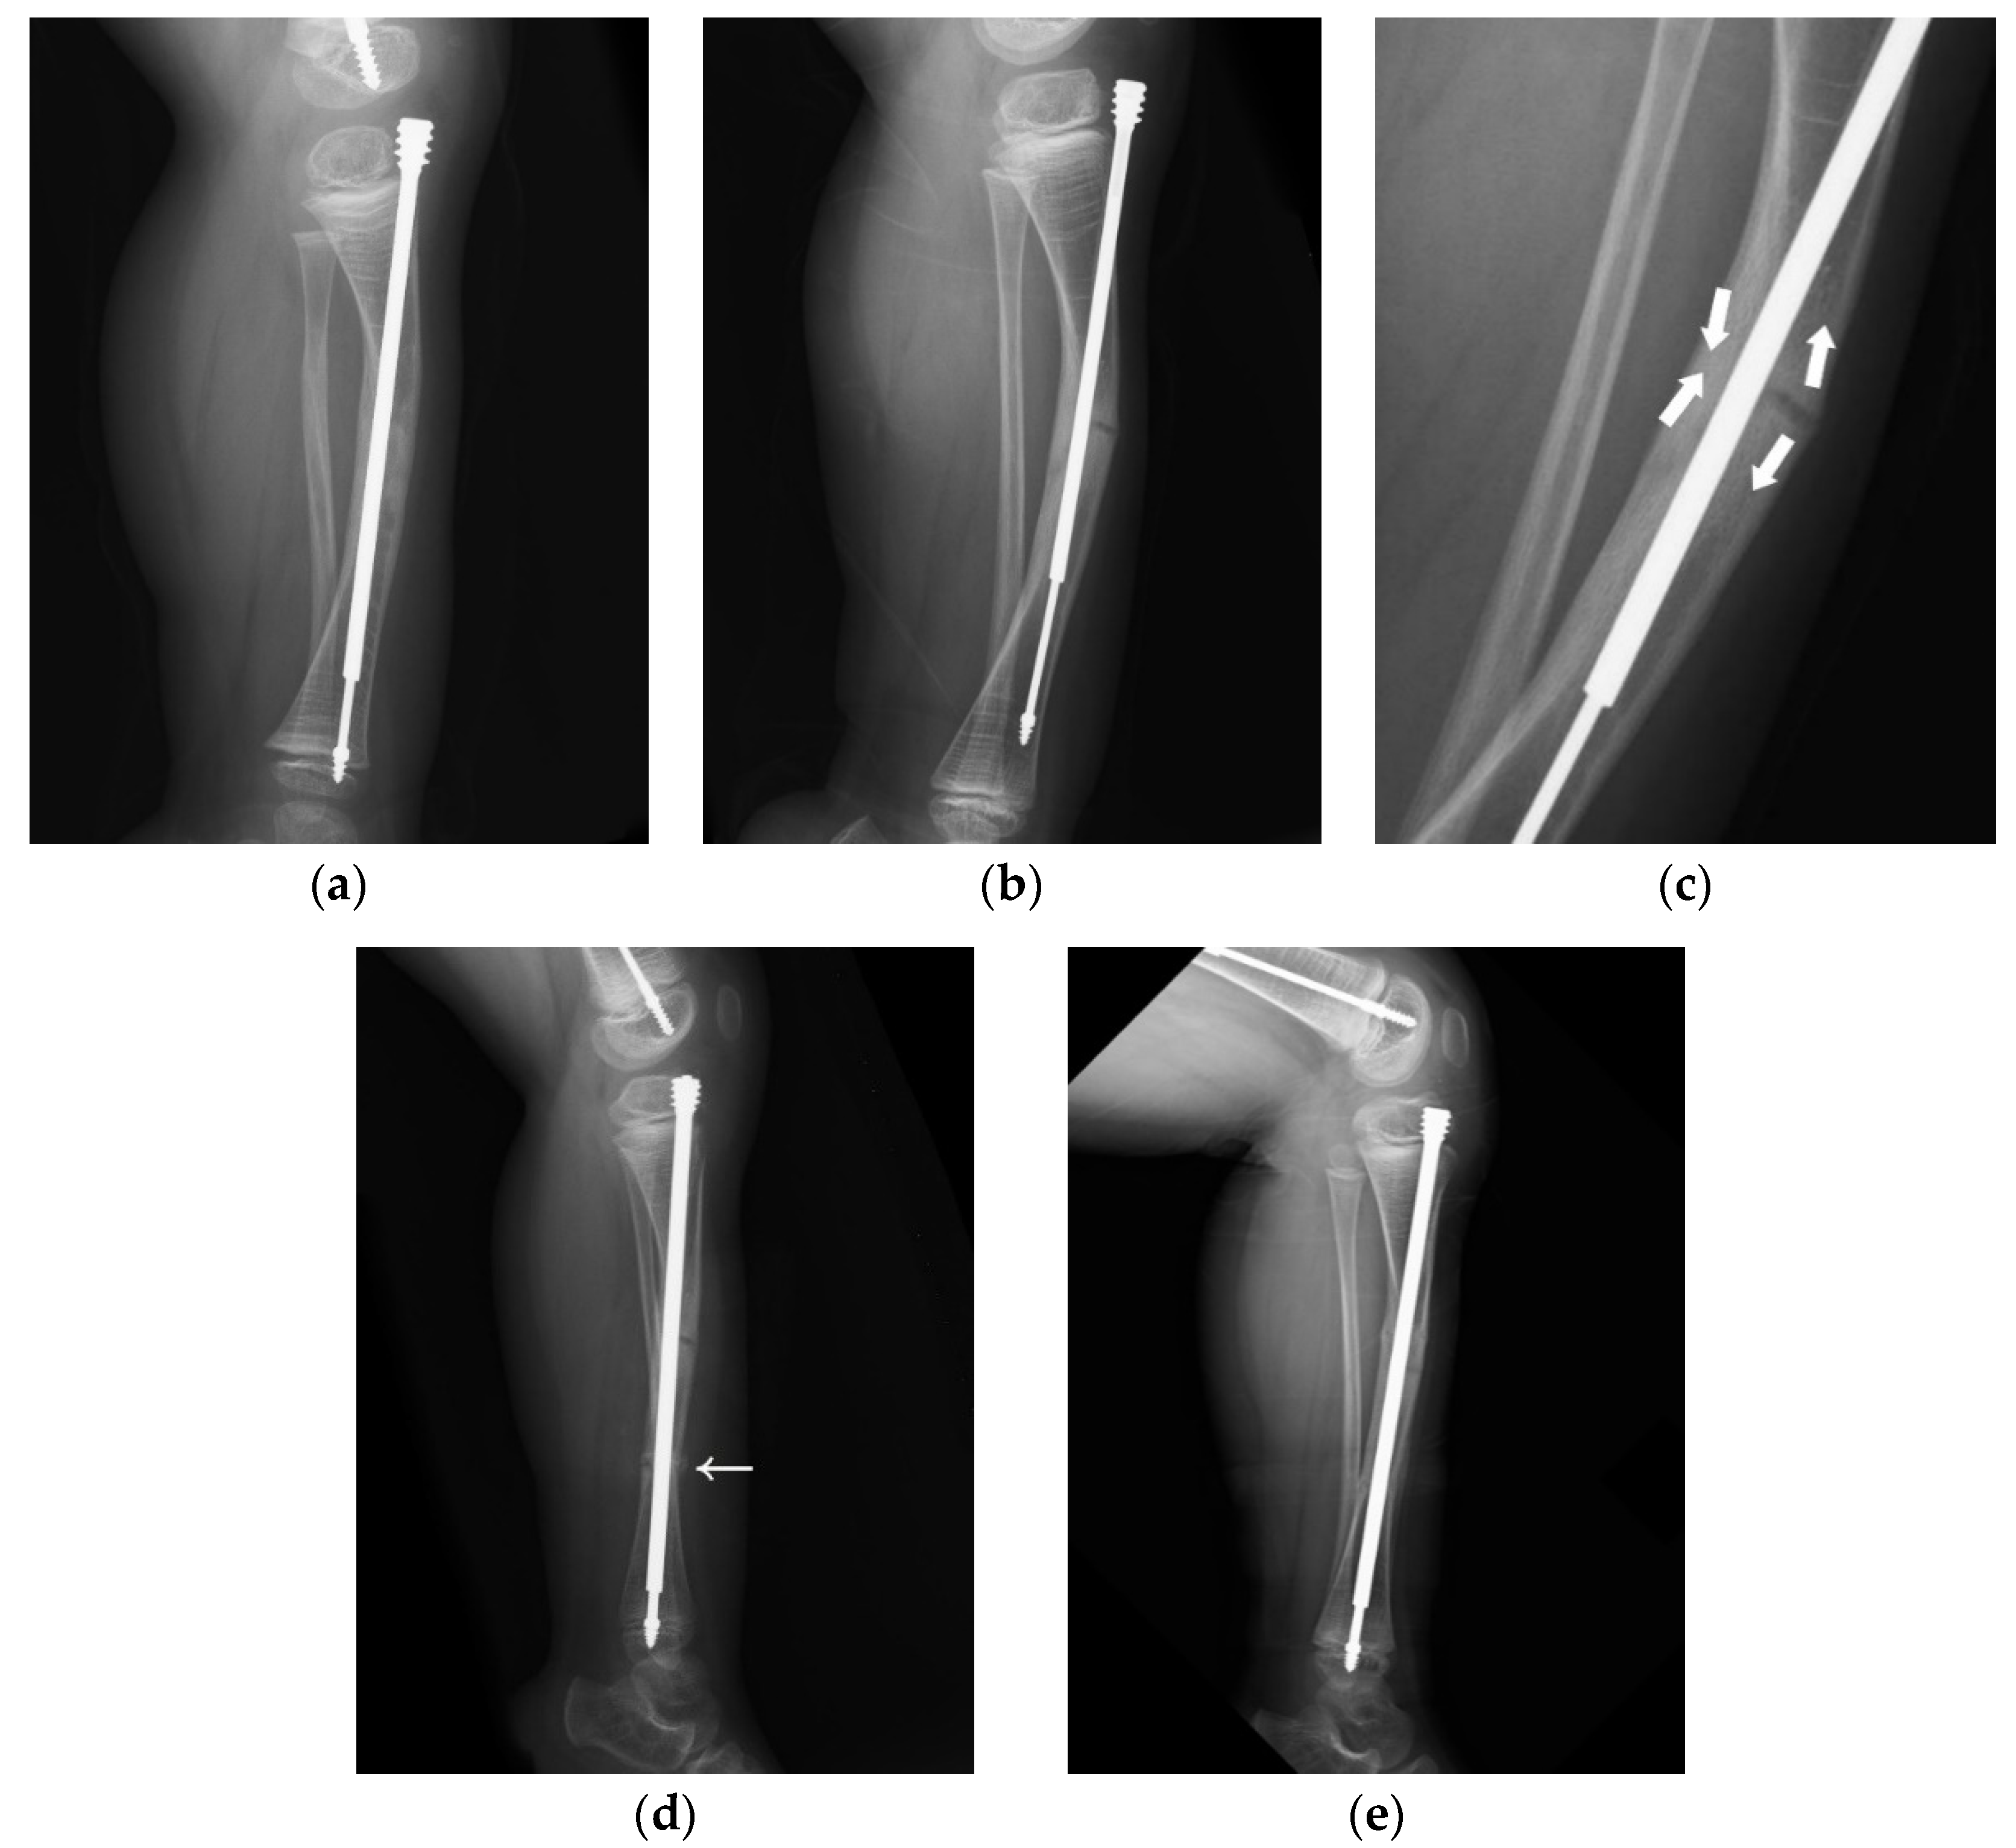

A 4-year-old male with type III OI presented as a classic model of insufficient depth of purchase and excessive bowing of the tibia (Figure 5). When axial force is applied to the limbs with excessive bowing, there will be an uneven force on the concave and convex sides, leading to delayed union (Figure 5a–c). Correction of the bowing with adequate osteotomy (or osteoclasis) before FD nail insertion is crucial (Figure 5d,e).

Figure 5. Lateral radiograph of the lower leg of a 4-year-old male post FD nail implantation. (a) There was insufficient depth of purchase into the epiphysis, and the position of the nail was anterior to the center of the epiphysis due to excessive bowing of the tibia. (b) As the patient grew, migration of the male implant (distal tibial nail pulled out of the epiphysis) was noted 2.5 years after implantation. (c) Excessive bowing resulted in uneven force applied to the concave and convex sides, which caused thickening of the cortex on the concave side and delayed union on the convex side. The aim of revision surgery was to correct bowing of the tibia with sufficient depth of purchase. (d) We corrected the bowing with adequate osteoclasis (arrow) before FD nail insertion. The position of the nail was at the center of the epiphysis in the lateral view after correcting for excessive bowing. (e) Good position of the FD nail and bone healing during regular follow-up.